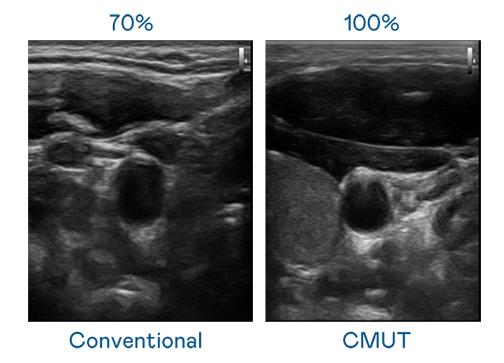

CMUT 技術是一種用電容式微機電元件來產生超音波訊號的技術。與傳統 PZT 壓電式技術相比,CMUT 頻寬增加 30%,更寬頻的超音波訊號讓影像解析度大幅提升,是實現高影像品質醫療超音波掃描、促進精準醫療發展的關鍵技術。

超音波影像的解析度高低,首先取決於探頭能發出的訊號頻寬。亿万28 CMUT 可提供高清晰的超音波訊號,提供高頻寬、高靈敏度、影像紋理細節更高的超音波影像,協助醫護人員縮短影像判讀時間及利用精準的醫療影像進行診斷。